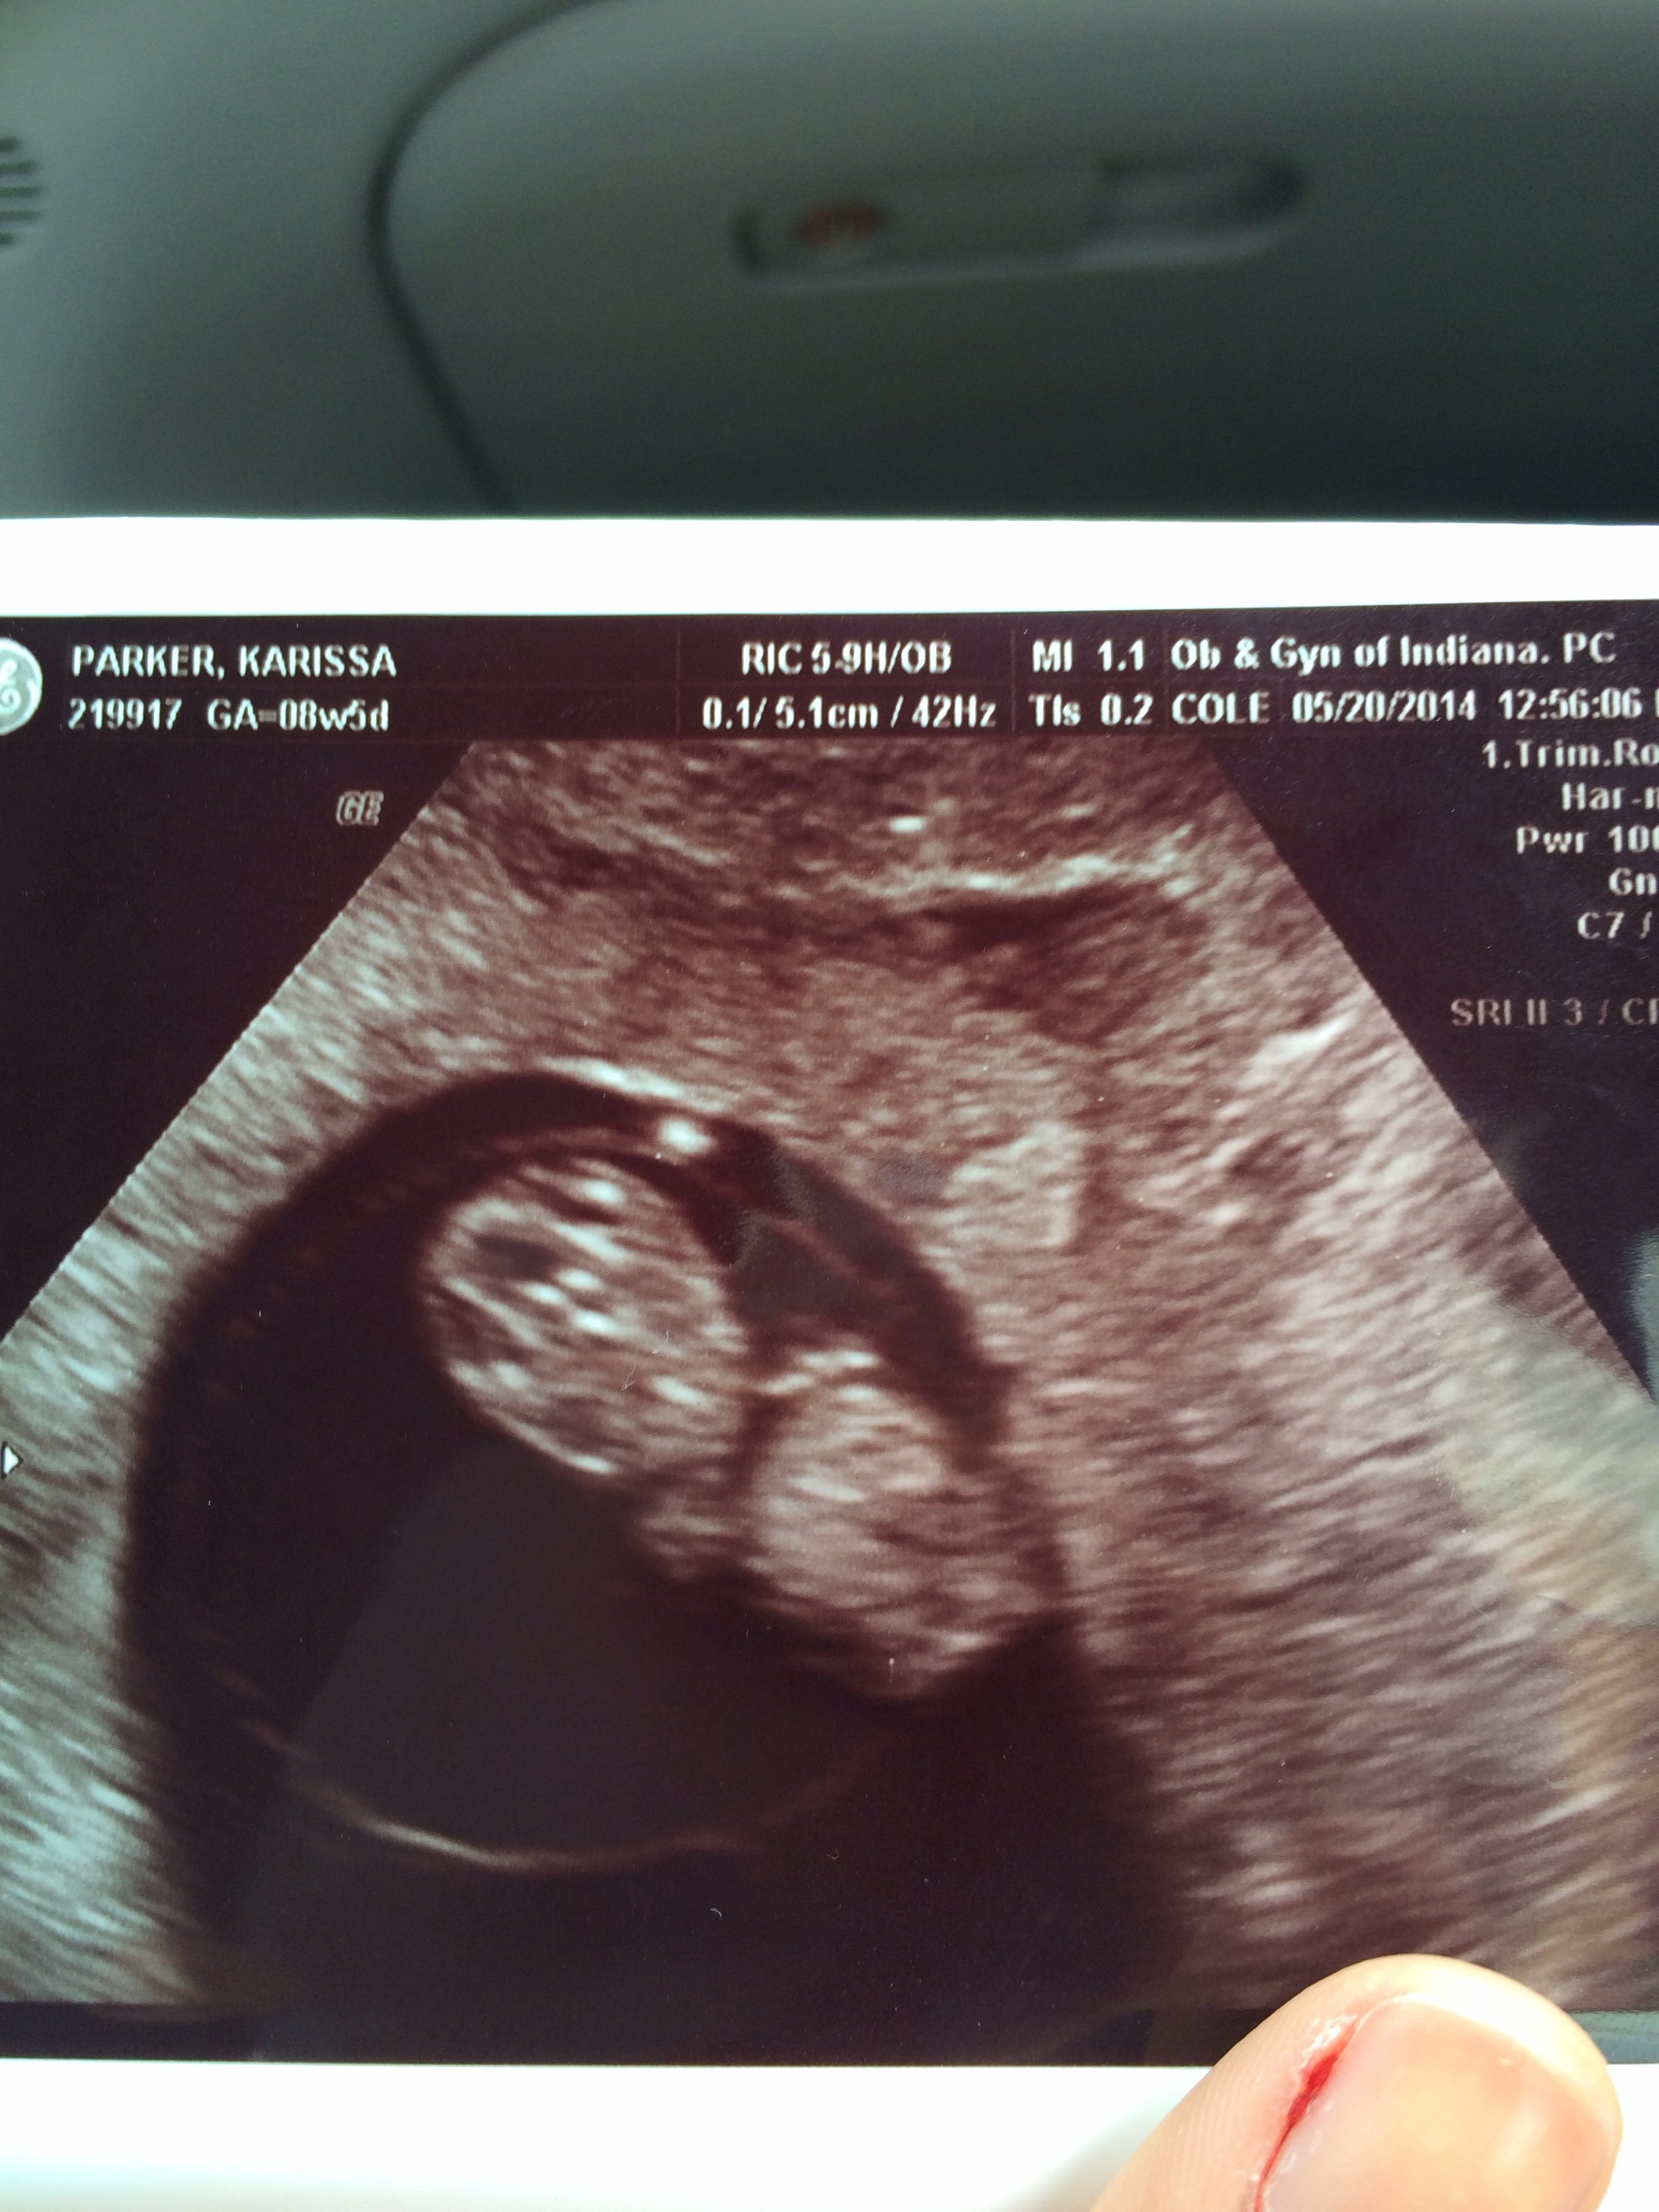

I had my first ultrasound today. My baby is measuring right where it should be, but my due date changed from the 26th to the 25th! A Christmas baby! Everything was perfect with a heart rate of 171bpm! Measuring at 8 weeks 5 days (: i couldn't be happier! I can finally take a breath of fresh air too.

I also had my first ultrasound yesterday morning and we found out that we are 8weeks and 5 days along!! WHich was pretty much on point with what was originally thought! So we too may be having a christmas baby!!!